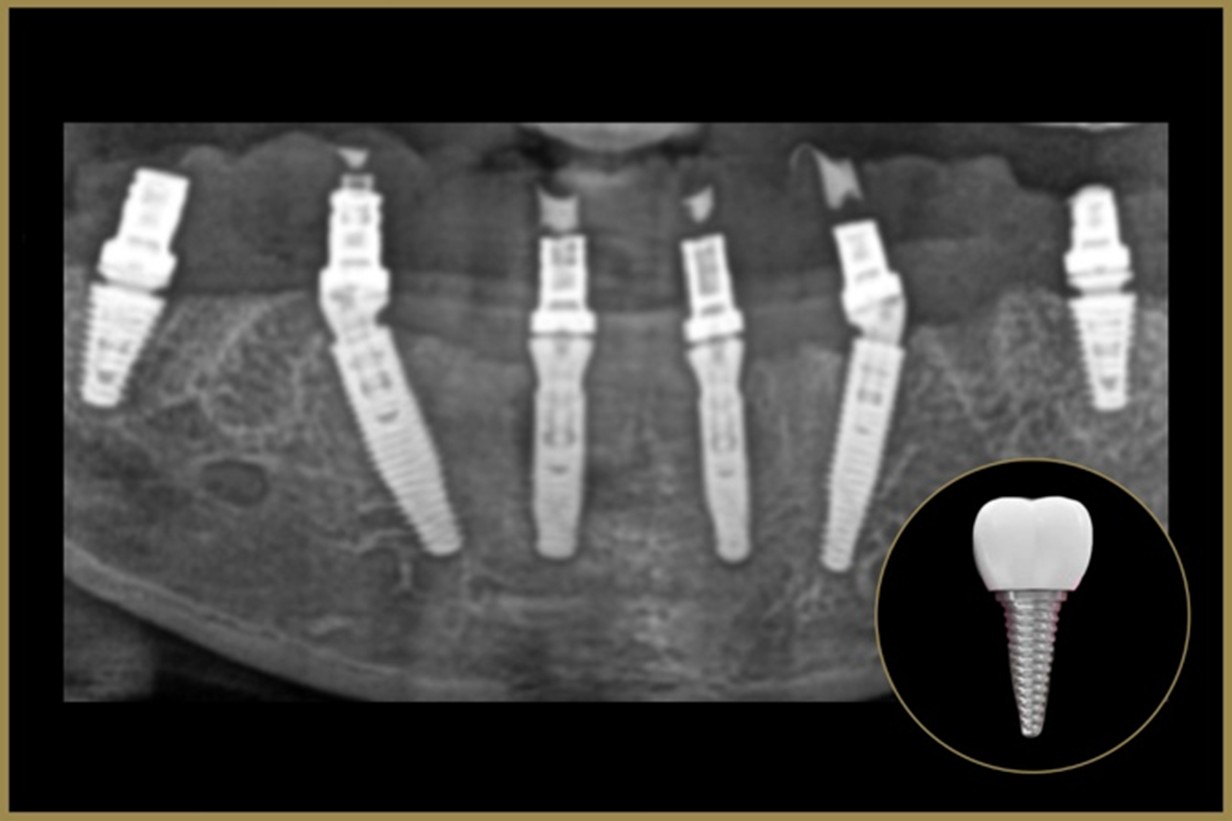

Digital X-rays, intraoral scanning, smile simulations, and computer-guided treatment planning.